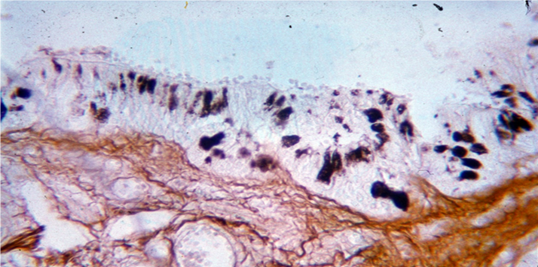

При гистологическом исследовании препаратов, окрашенных по методу Гримелиуса, с использованием иммуногистохимической реакции, в СОГ и железах обнаружены апудоциты различной формы (округлой, трапециевидной, треугольной и овальной) и окраски (от светлого до темно-коричневого цвета) (рис. 6, 7).

Рис. 6. Аргирофильные гранулы в апудоцитах СОГ.

Гистохимическая окраска по Гримелиусу, х400

Рис. 7. Серотонинсодержащие апудоциты в СОГ. Иммуногистохимическая реакция, х600

Источник: составлено авторами на основе [7].

Морфометрический анализ показал, что в экспериментальной группе количество АПУД-клеток и серотонинпродуцирующих апудоцитов значительно превышало аналогичные показатели в контрольной группе (табл. 2).

Возможно, что физическое переутомление (длительное плавание) адаптирует организм животных к стрессу [6]. Это приводит, по данным собственного исследования, к развитию острой аноксии, способствующей повышению уровня серотонина в крови и гиперплазии серотонинпродуцирующих апудоцитов в мышцах гортани, что сопровождается развитием ларингоспазма и утопления по асфиктическому типу. Кроме того, известно что в легких здорового человека количество аргирофильных и серототонинсодержащих апудоцитов существенно больше у плодов и новорожденных детей, меньше - у взрослых; их соотношение составляет 4 : 1 [3]. Показано, что при различных патогенетических типах утопления и острых пневмониях у детей, сопровождающихся развитием гипоксии, число аргирофильных и серотонинпродуцирующих апудоцитов значительно увеличивается [7; 8], что согласуется с результатами собственного исследования.

Данные литературы свидетельствуют, что особенности патогенеза асфиктического типа утопления до конца не изучены. Считается, что фактором, определяющим наступление смерти при данном типе утопления, является развитие рефлекторного ларингоспазма в связи с попаданием воды в носоглотку и гортань [4; 9; 10, с. 258]. Наряду с этим тонкие механизмы развития ларингоспазма на клеточном уровне с участием АПУД-системы воздухоносных путей практически не изучены. В связи с этим выявленное с помощью иммуногистохимического и морфометрического анализа значительное увеличение содержания серотонинпродуцирующих апудоцитов в слизистой оболочке гортани может являться, наряду с другими морфологическими проявлениями (эмфизема легких, воздушная эмболия левых отделов сердца, мелкоточечные субплевральные кровоизлияния [11, c. 168; 12, c. 282; 13]), одним из дополнительных диагностических признаков асфиктического типа утопления [7]. Результаты исследования подтверждают известную аксиому о том, что не может быть нарушения функции без нарушения структуры и «даже ничтожнейшие функциональные изменения не могут возникнуть и исчезнуть, не отразившись в соответствующих структурных изменениях на молекулярном или ультраструктурном уровне» [14, с. 327].